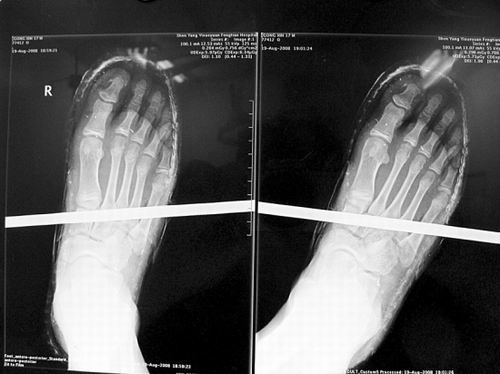

X光片顯示無(wú)大礙

事發(fā)時(shí)男孩穿著一雙布鞋,骨外二科陳賓醫(yī)生操起剪刀,將布鞋一塊塊剪掉。經(jīng)X光透視,醫(yī)生驚奇地發(fā)現(xiàn):男孩雖然被鋼筋穿透了右腳,但骨頭、大的血管和神經(jīng)都沒(méi)受任何傷害!

20日,記者從X光片子上看到,鋼筋避開了男孩腳掌骨頭密集的部位,而是從腳弓處穿過(guò),這個(gè)部位基本上以軟組織為主!罢鏇](méi)想到,太神奇了!”幾名醫(yī)生連聲感嘆,術(shù)中,他們分工合作,小心翼翼地將鋼筋取出,并做了引流、清創(chuàng)、包扎。